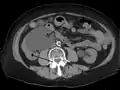

Left sided hydronephrosis in a person with an atrophic right kidney. Stent is also present (image below).

Left sided hydronephrosis, coronal view. Stent is also present.

Treatment of hydronephrosis focuses upon the removal of the obstruction and drainage of the urine that has accumulated behind the obstruction. Therefore, the specific treatment depends upon where the obstruction lies.[12]

Acute obstruction of the upper urinary tract is usually treated by the insertion of a nephrostomy tube. Chronic upper urinary tract obstruction is treated by the insertion of a ureteric stent or a pyeloplasty.[11]